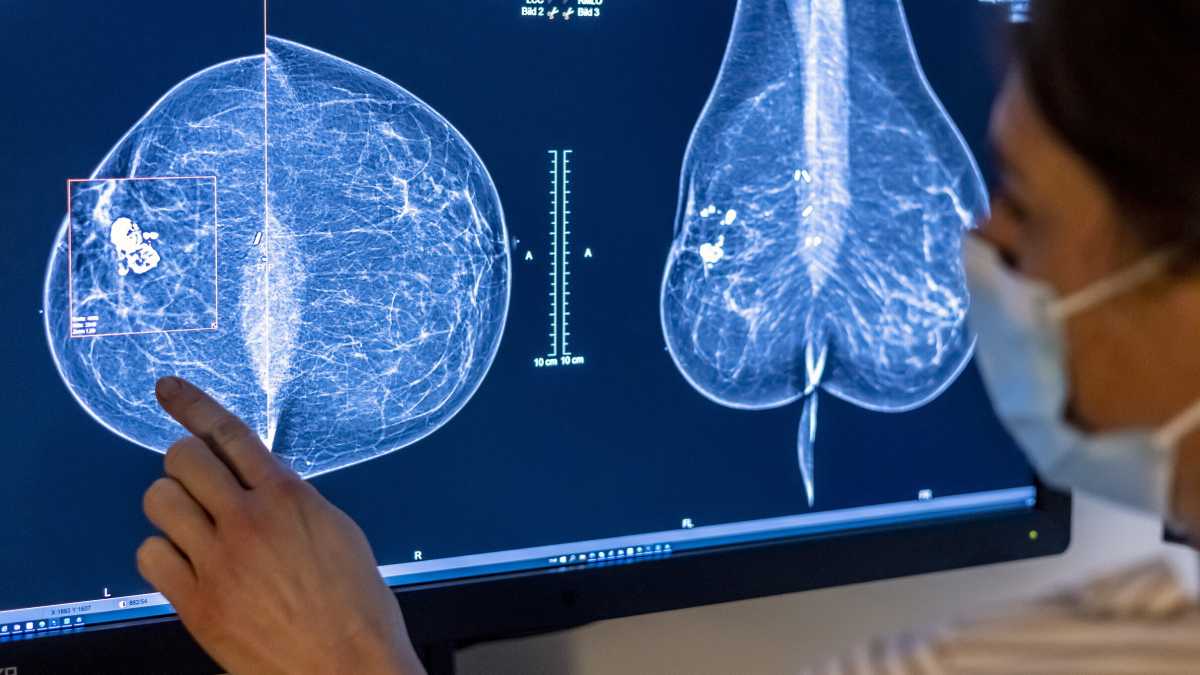

Berlino, il personale medico usa una mammografia per esaminare il seno di una donna (Foto di Michael Hanschke/Getty Images) <br />

In questo contesto si inserisce un recente studio appena pubblicato su Nature Medicine, che analizza come l'IA possa essere utilizzata per migliorare lo screening mammografico e il rilevamento del cancro al seno. Questo studio è stato condotto in Germania e ha coinvolto oltre 460.000 donne, con l'obiettivo di valutare l'efficacia di un sistema IA nel supportare i radiologi durante la doppia lettura delle mammografie, un processo essenziale per garantire la qualità degli screening. I risultati mostrano che l'IA ha permesso di scoprire più tumori senza aumentare inutilmente i falsi allarmi, riducendo anche il carico di lavoro per i radiologi.